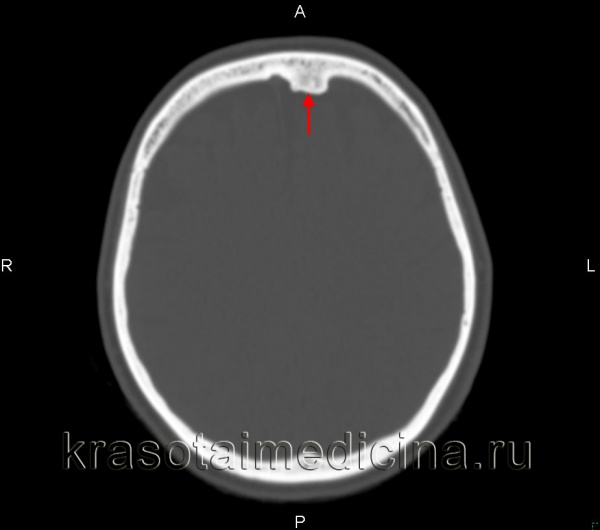

(Справа) На аксиальной КТ в костном окне определяется плотная компактная остеома правой лобной пазухи, пересекающая срединную линию, рас пространяющаяся влево и интракраниальною обеих лобных пазухах присутствует «запертый» секрет. Остеомы чаще обнаруживаются в лобных пазухах, чем в любых других. (Слева) На аксиальной КЛКТ определяется губчатая остеома передней стенки правой верхнечелюстной пазухи. Остеома состоит из ядра, представленного губчатой костью, покрытого толстой и ровной кортикальной пластинкой.